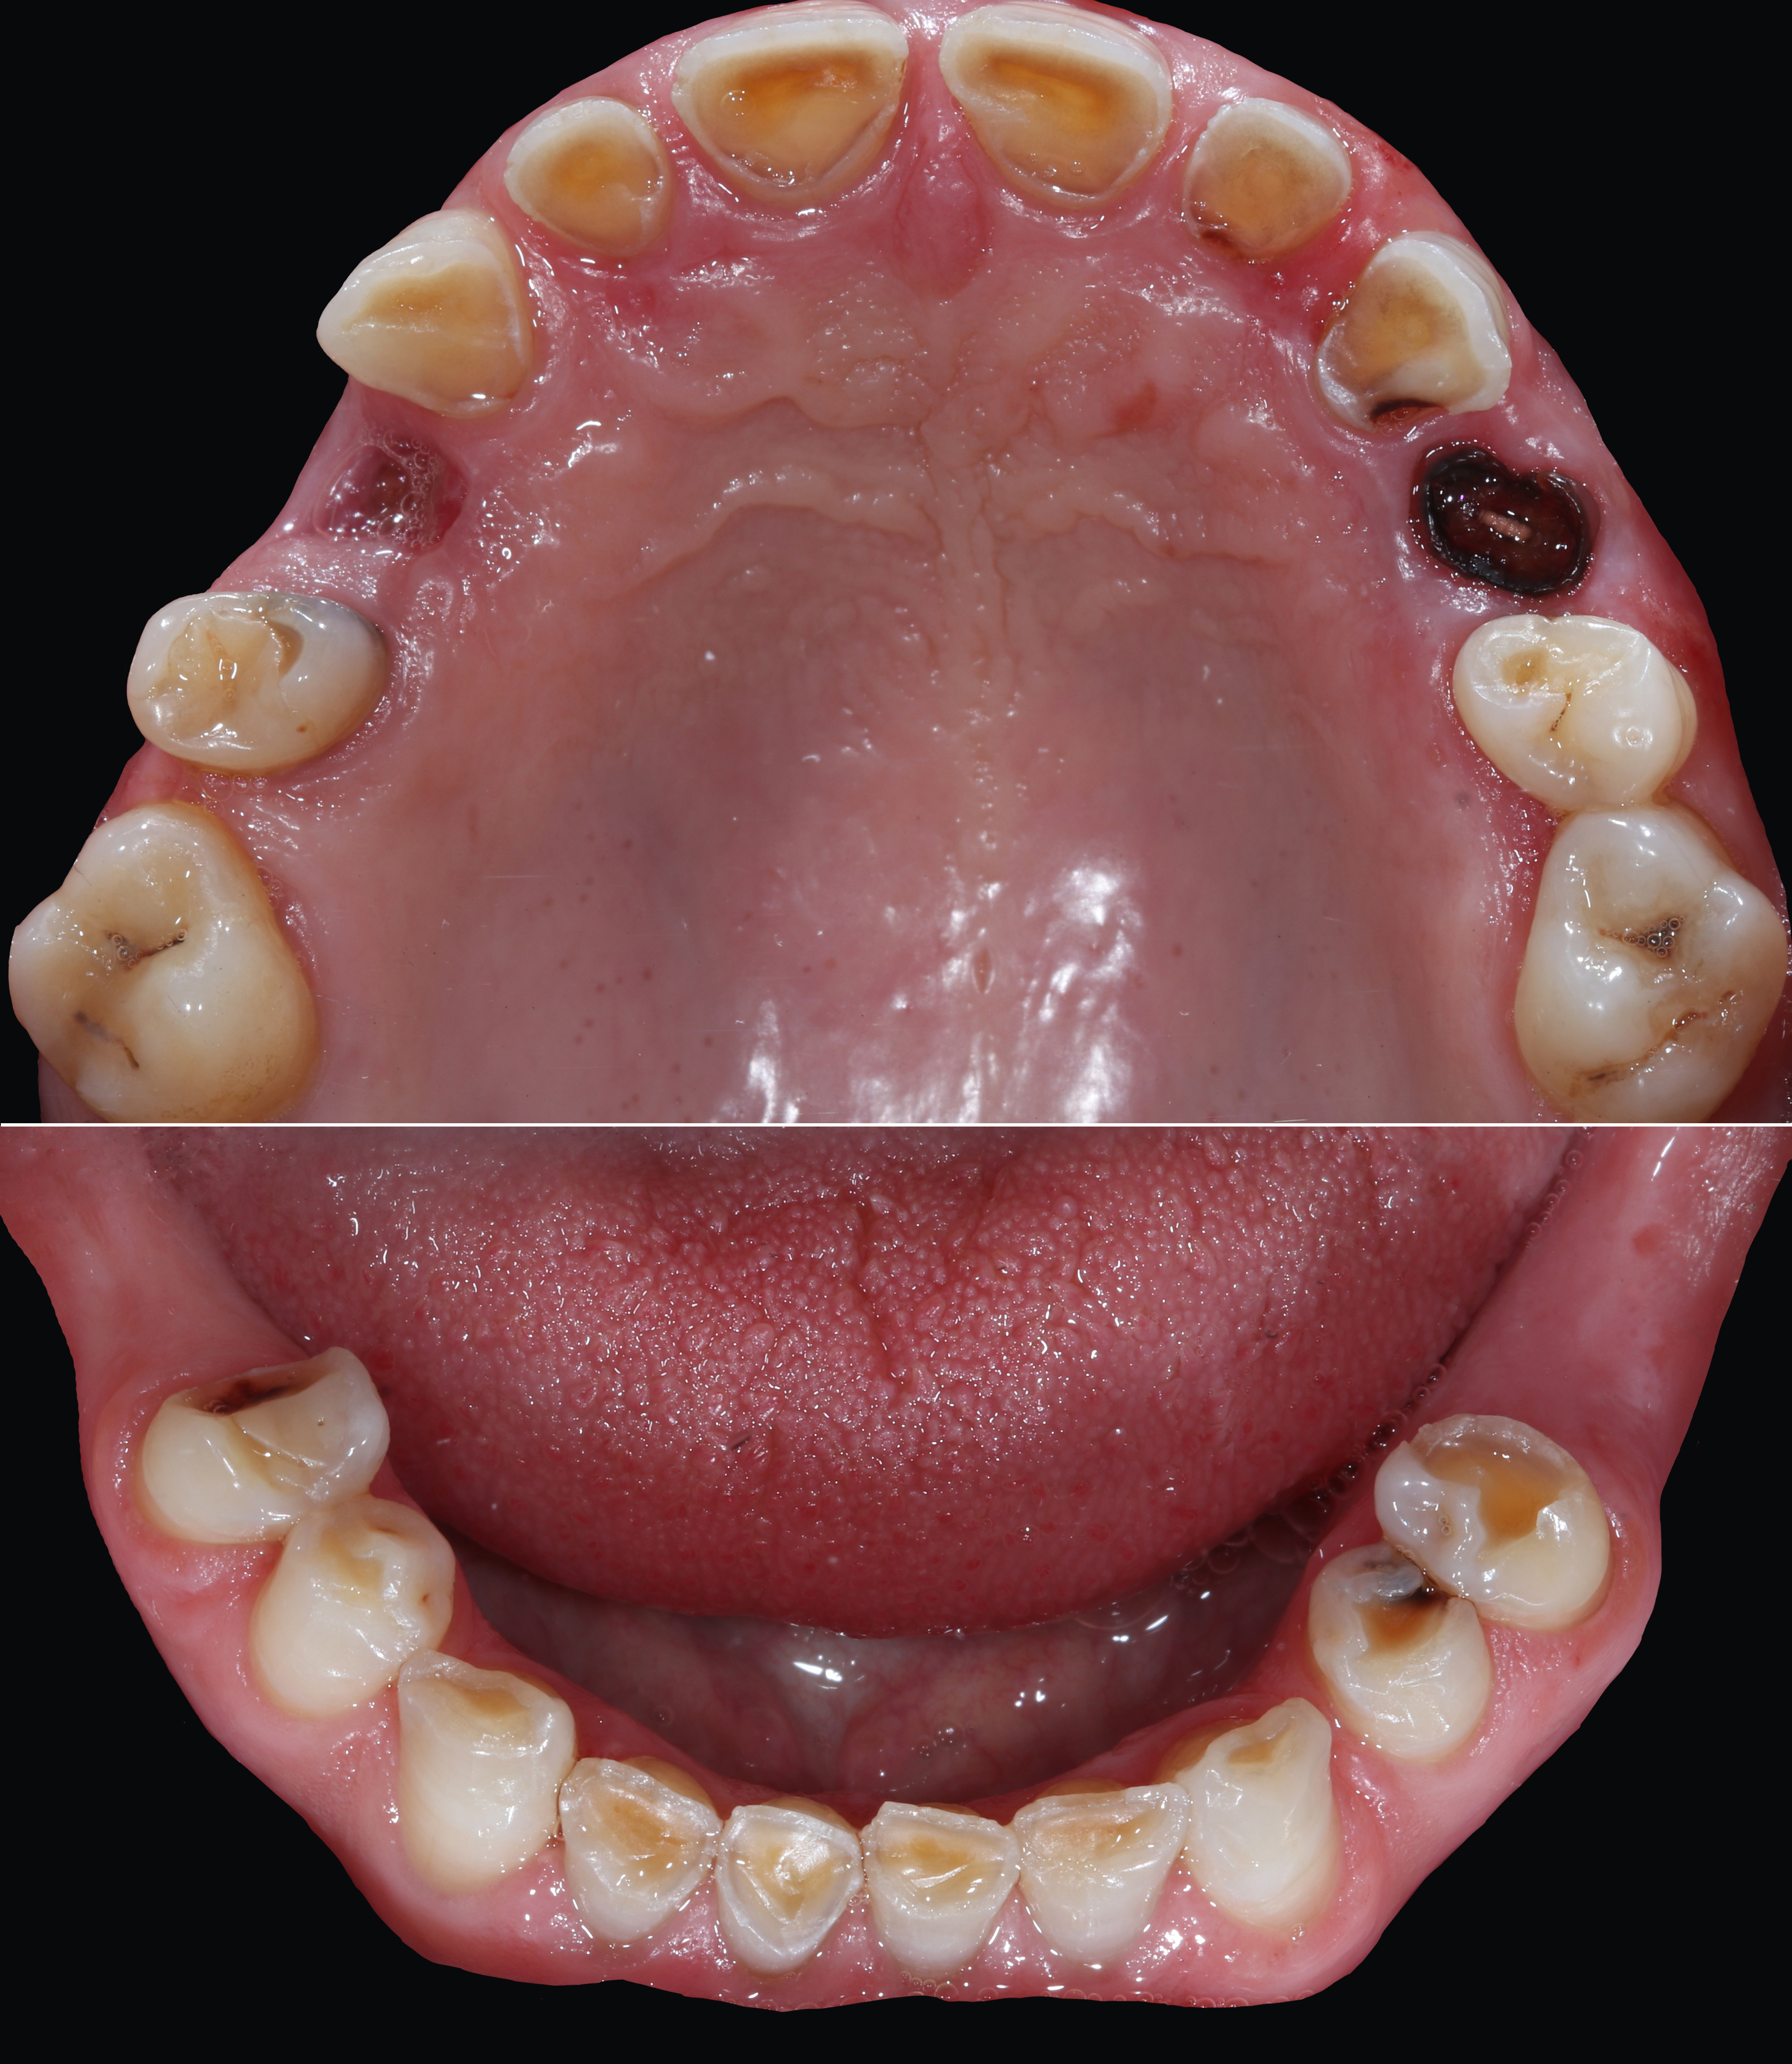

Ασθενής με αποδιοργανωμένη, εκτενώς φθαρμένη οδοντοφυΐα, τερηδόνες και κατεστραμμένα δόντια στην άνω γνάθο που προκαλούσαν έντονους πόνους, προσήλθε στο Aesthetic Dental Studio στην Καλαμάτα με στόχο την αισθητική και λειτουργική αποκατάσταση του στόματός της.

Σε πρώτη φάση, αφαιρέθηκαν τα δόντια που ήταν πλήρως κατεστραμμένα, πραγματοποιήθηκαν ενδοδοντικές θεραπείες στα δόντια που μπορούσαν να αποκατασταθούν και έγιναν εμφράξεις σε δόντια με απλή τερηδόνα. Έτσι, το στόμα σταθεροποιήθηκε και ήταν πλέον έτοιμο για την δεύτερη φάση της θεραπείας, που περιελάμβανε την προσθετική αποκατάσταση των δοντιών.

Πραγματοποιήσαμε ψηφιακό διαγνωστικό «κέρωμα», και τα τρισδιάστατα εκτυπωμένα εκμαγεία της ασθενούς τοποθετήθηκαν σε γναθολογικό μηχάνημα (ημιπροσαρμοζόμενος αρθρωτήρας) ούτως ώστε να αξιολογήσουμε:

Στην συνέχεια, κατασκευάστηκαν προσωρινές ακρυλικές αποκαταστάσεις καθ' εικόνα και ομοίωση του διαγνωστικού κερώματος ώστε τα παραπάνω να εξετασθούν και στην πράξη στο στόμα της ασθενούς.

Τελική προσθετική αποκατάσταση

Αφού όλα επιβεβαιώθηκαν, έγινε λήψη ψηφιακών αποτυπωμάτων με ενδοστοματικό σαρωτή και στην συνέχεια τοποθετήθηκαν ακίνητες κεραμικές αποκαταστάσεις ολικής επικάλυψης (στεφάνες και γέφυρες).

Το τελικό αποτέλεσμα ήταν αισθητικά άρτιο και λειτουργικά σταθερό, προσαρμοσμένο στις ανάγκες της ασθενούς.